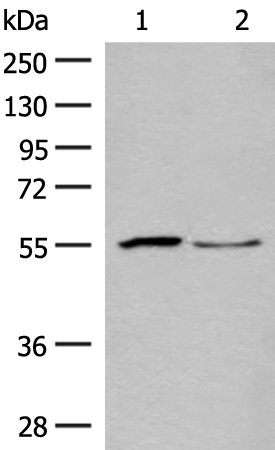

分类: 科研抗体货号: P13465别名: GA; GLS; LGA; hLGA应用: WB,IHC反应种属: Human, Mouse, Rat